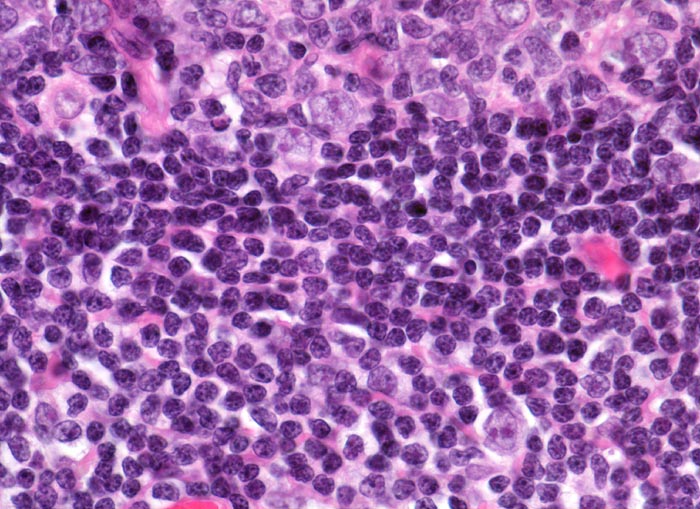

normaler Lymphknoten: Mantelzone und Marginalzone

Oben im Bild ein Keimzentrum mit Zentrozyten, Zentroblasten und follikulär dendritischen Zellen. Angrenzend die zelldichte Mantelzone. Unten im Bild die lockerer konfigurierte Marginalzone mit eingestreuten dendritischen Zellen mit sternförmigen Zytoplasmaausläufern und Blasten mit grossen Kernen.

Perikolischer tumorfreier Lymphknoten aus dem Abflussgebiet eines wenig fortgeschrittenen Kolonkarzinoms.

630